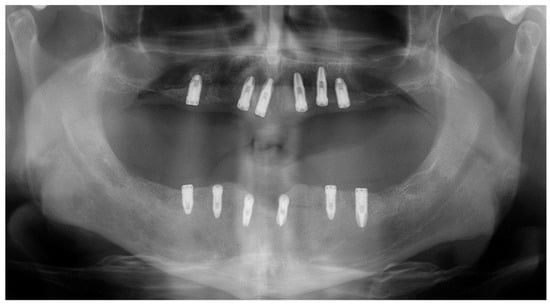

Immediate reconstruction of the defect was performed with an inferiorly based FAMM flap (Figure 3 and Figure 4) and immediate placement of 12 dental implants, 6 in the mandible and 6 in the maxilla (Figure 5). There were no postoperative complications, and the patient received postoperative radiotherapy (60 Gy). Eight months later, prosthetic rehabilitation of the dental implants was performed, and the aesthetic and functional evaluations were accomplished.

Mouth opening was evaluated as normal and lingual mobility as excellent for tip elevation, lingual protrusion, and lateral movements (Figure 6 and Figure 7). The patient was rehabilitated with two implant-supported prostheses (Figure 8, Figure 9 and Figure 10). Their speech articulation was evaluated as normal and the patient reported a normal diet without restrictions. From the aesthetic point of view, the patient reported an excellent result (Figure 11).

Figure 5. Immediate dental implants in both the maxilla and mandible for functional rehabilitation after teeth extraction.

Jcm 10 03625 g005